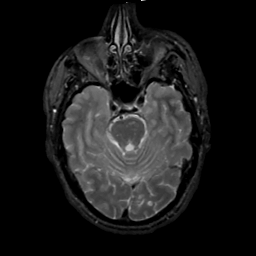

MR Study #1, February 10, 1991 -- Slice #16

[Home][Help][Clinical][Tour 1][Tour 2] Slice 16